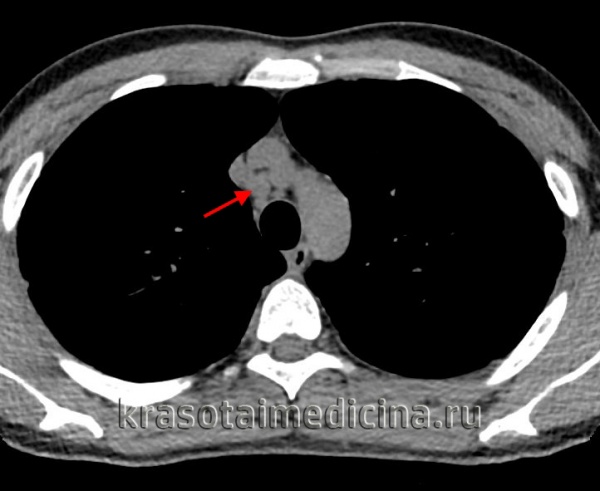

КТ органов грудной клетки. Множественные типичные саркоидозные очаги субмиллиметрового диапазона с диффузным распространением

При проведении бронхоскопии с биопсией могут обнаруживаться косвенные и прямые признаки саркоидоза: расширение сосудов в устьях долевых бронхов, признаки увеличения лимфоузлов в зоне бифуркации, деформирующий или атрофический бронхит, саркоидные поражения слизистой оболочки бронхов в виде бляшек, бугорков и бородавчатых разрастаний. Наиболее информативным методом диагностики саркоидоза служит гистологическое исследование биоптата, полученного при бронхоскопии, медиастиноскопии, прескаленной биопсии, трансторакальной пункции, открытой биопсии легких. Морфологически в биоптате определяются элементы эпителиоидной гранулемы без некроза и признаков перифокального воспаления.